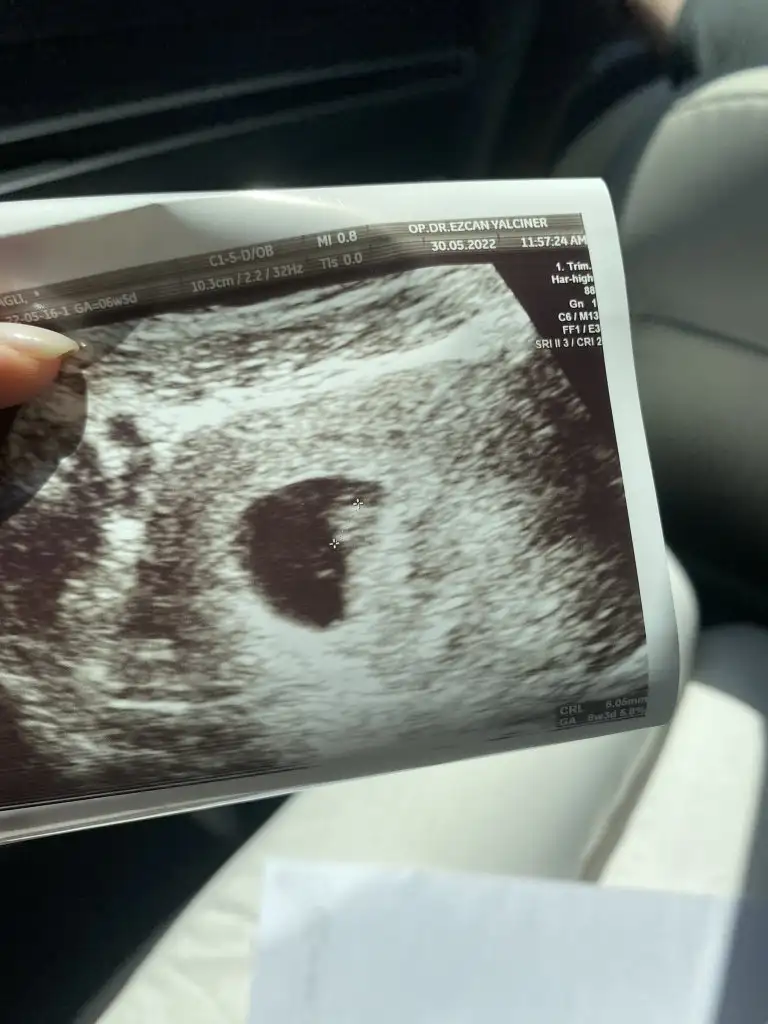

Ben birşey merak ediyorum dun doktora ilk defa gittim karından muayenede goremedı alttan muayenede 5 haftalık dedı ama ultrasyonda boyle kesenın ıcınde bırsey yok bombos duruyor adet tarıhıme gore hesaplama yaptı ama ben 5 haftalık oldugunu sanmıyorum